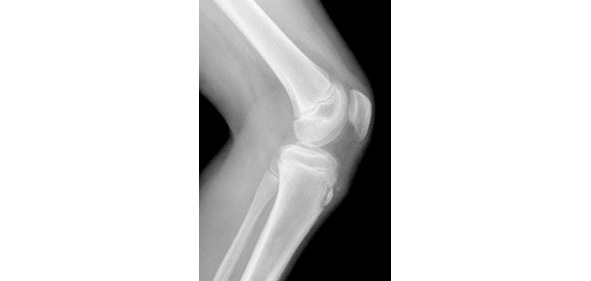

Одним из заболеваний, при которых рекомендовано применение кинезиологического тейпирования является болезнь Осгуда—Шлаттера. Данное заболевание относится к категории остеохондропатий и проявляется в виде формирования остеохондропатии бугристости большеберцовой кости. Болезнь Осгуда-Шлаттера развивается преимущественно у молодых лиц в возрасте от начала периода полового созревания до 18 лет. Риск развития болезни у мужчин значительно выше. Что является немаловажным фактом это патогенез формирования остеохондропатии бугристости большеберцовой кости, который во многом связан с физическими нагрузками и профессиональным занятием спортом.

Рисунок 15. Рентгенологические признаки болезни Осгуда-Шлаттера

Наиболее подвержены развитию данного заболевания лица, занимающиеся такими видами спорта, как футбол, гандбол, баскетбол, хоккей, волейбол, легкая и тяжелая атлетика, горные лыжи, большой теннис, дзюдо, самбо, керлинг, кикбоксинг, балет, ирландские танцы, бальные танцы и др. Клиническая картина болезни Осгуда—Шлаттера представлена болями, возникающими при сильном разгибании или крайнем сгибании в коленном суставе. В дальнейшем это приводит к формированию ограниченной, плотной, резко болезненной при пальпации припухлости большеберцового бугра. Данные изменения обусловлены выраженными или даже чрезмерными спортивными нагрузками на сухожилие четырехглавой мышцы бедра, прикрепляющееся к бугристости большеберцовой кости (рис. 15, 16). На фоне ускоренного темпа роста в подростковом возрасте, систематические нагрузки на четырёхглавую мышцу, приводят к давлению на незрелую бугристость большеберцовой кости, и могут спровоцировать подострый отрывной перелом последней в сочетании с развитием тендинита. В дальнейшем это приводит к формированию патологических костных разрастаний, болезненных при резких движениях. При опоре на колено боль может давать иррадиацию по ходу сухожилия.